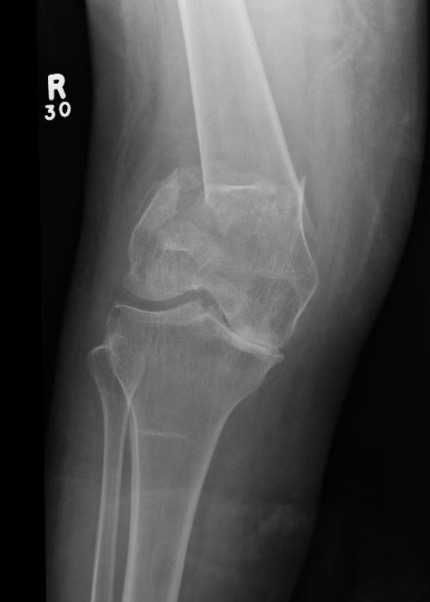

AO Type B1 & B2: Partial articular

![]()

Definition

Medial or lateral sagittal split

Technique

ORIF

- medial or lateral approach based on fracture location

- reduce articular split and fix with screws

- medial or lateral buttress plate

Lateral split fracture distal femur